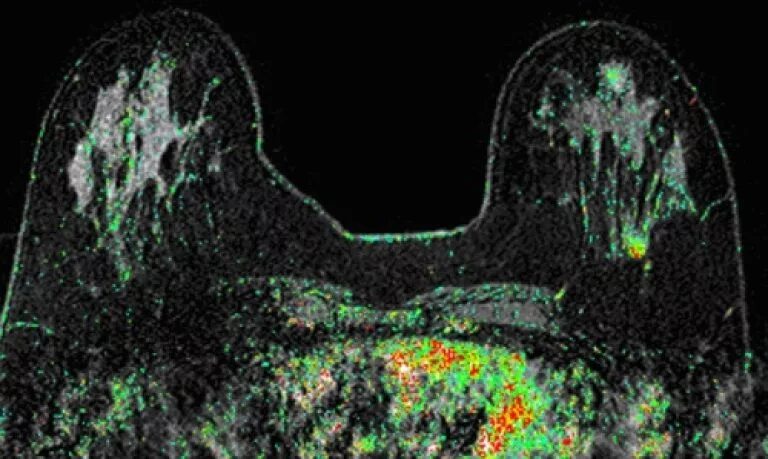

Мрт молочных желез